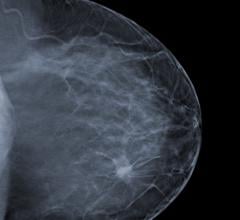

The digital breast tomosynthesis (DBT) market continues to evolve, with reportedly no less than six new systems prepping to hit the market in the near future. At the 2015 Radiological Society of North America (RSNA) annual meeting, Liane Philpotts, M.D., professor of diagnostic radiology and chief of breast imaging at Yale University, discussed how tomosynthesis is revolutionizing breast imaging.

Despite decades of progress in breast imaging, one challenge continues to test even the most skilled radiologists ...